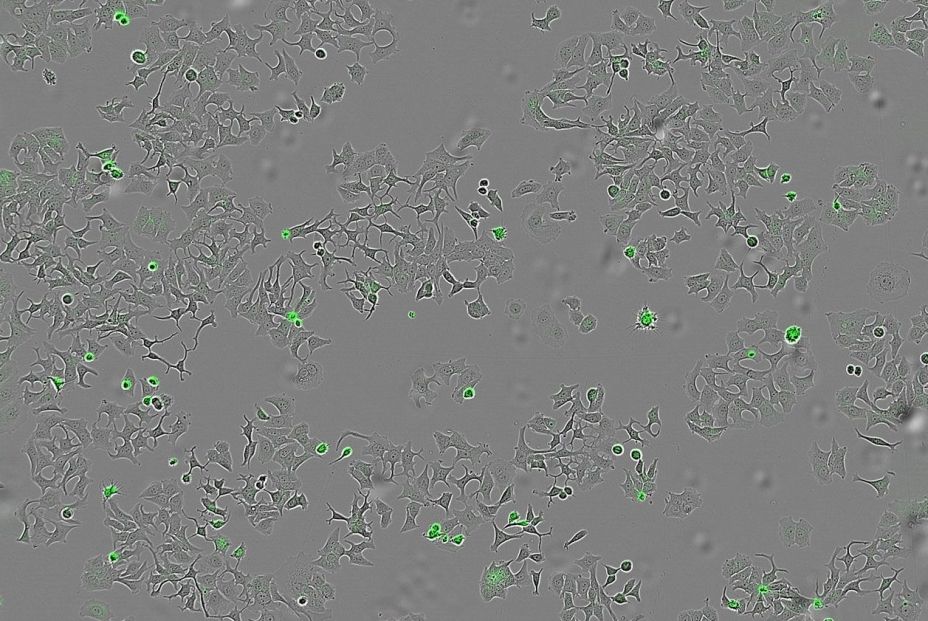

A la hora de desarrollar esta investigación se ha cultivado una cepa normal y otra mutante modificada genéticamente de la bacteria Vibrio cholerae, y posteriormente se ha recogido supernatante, el líquido donde crecen estas bacterias y que también contiene las proteínas y sustancias liberadas por la bacteria, para después aplicarlo a células cancerosas humanas de colon, mama y páncreas para observar qué efectos producía.

Los científicos han empleado tanto el cultivo bacteriano original como bacterias inocuas artificialmente modificadas para producir solo HapA, demostrando que el efecto es realmente causado por esta proteína concreta y no por otros posibles factores de la bacteria. Además, han comparado igualmente los resultados con el supernatante de una bacteria diferente que no produce HapA, como la Escherichia coli.

"Lo que buscamos fue comprobar si las células humanas de distintos tipos tumorales (mama, colon y páncreas) seguían vivas y si podían multiplicarse tras estar en contacto con estas sustancias bacterianas, en particular con la proteína HapA", ha explicado Hurtado.

Durante el proceso, se han empleado sistemas avanzados de imagen en tiempo real que permiten contar células vivas y muertas, y medir la apoptosis para observar con precisión el bloqueo de las vías. La investigación ha recibido financiación del Consejo de Investigación Sueco, la Sociedad de Cáncer de Suecia, la Unión Europea y la Universidad de Umea (Suecia).